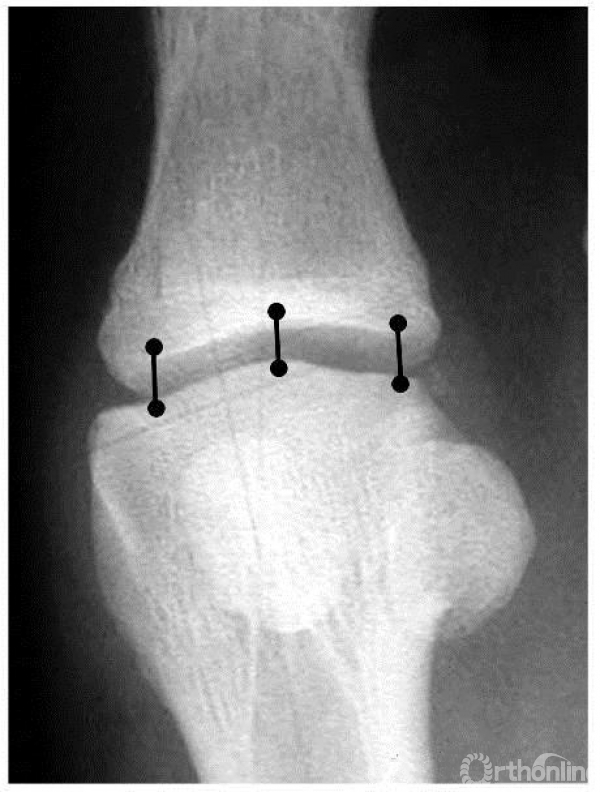

关节间隙测量方法

正位X线上:选择两端关节面的内侧、中间、外侧三点,分别连线

侧位X线上:选择两端关节面的背侧、中间、跖侧三点,分别连线

取上述六个连线长度平均值,即为关节间隙大小